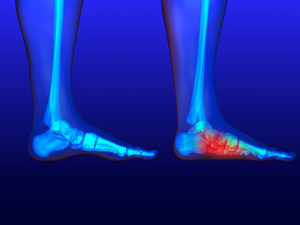

There is a portion of the foot that contains a narrow space which is located on the inside of the . This is referred to as the tarsal tunnel. If this area becomes inflamed as a result of an injury, tarsal tunnel syndrome may develop. The symptoms that are often associated with this condition can include swelling, pain and discomfort surrounding the , and patients may feel a tingling or burning sensation. Moderate relief may be found when the affected foot is taped, as this may help to keep it from moving. Additionally, wearing orthotic inserts may provide adequate cushioning as the healing process occurs. If you feel you have developed this condition, it is strongly suggested that you consult with a podiatrist who can offer you the correct treatment.

Tarsal tunnel syndrome, which can also be called tibial nerve dysfunction, is an uncommon condition of misfiring peripheral nerves in the foot. The tibial nerve is the peripheral nerve in the leg responsible for sensation and movement of the foot and calf muscles. In tarsal tunnel syndrome, the tibial nerve is damaged, causing problems with movement and feeling in the foot of the affected leg.

A physical exam of the leg can help identify the presence of tarsal tunnel syndrome. Medical tests, such as a nerve biopsy, are also used to diagnose the condition. Patients may receive physical therapy and prescriptive medication. In extreme cases, some may require surgery.